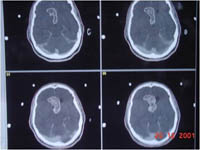

Radiosurgery Gallery